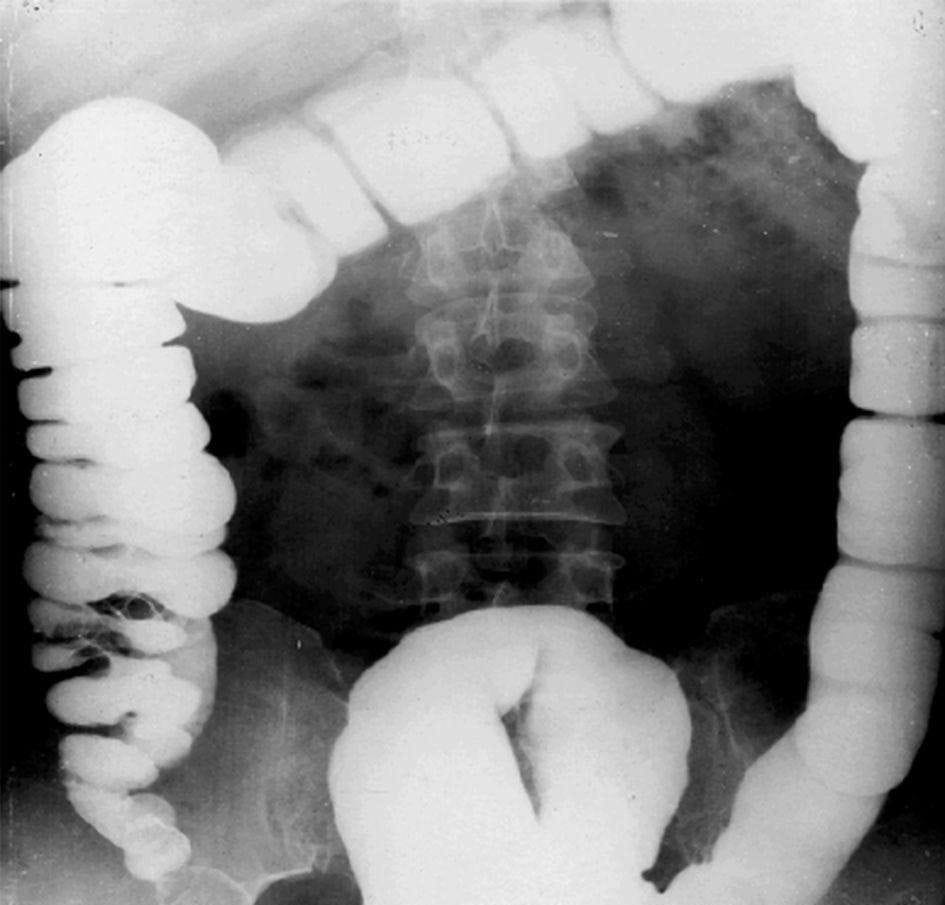

肠梗阻常见原因:动力性、麻痹性、痉挛性: 机械性(最为常见)、单纯性(无血运障碍)、绞窄性(有血运障碍)、血运性(肠系膜动脉血栓)。

急性小肠梗阻:小肠扩张积气,小肠腔内积液,结肠内气体少。